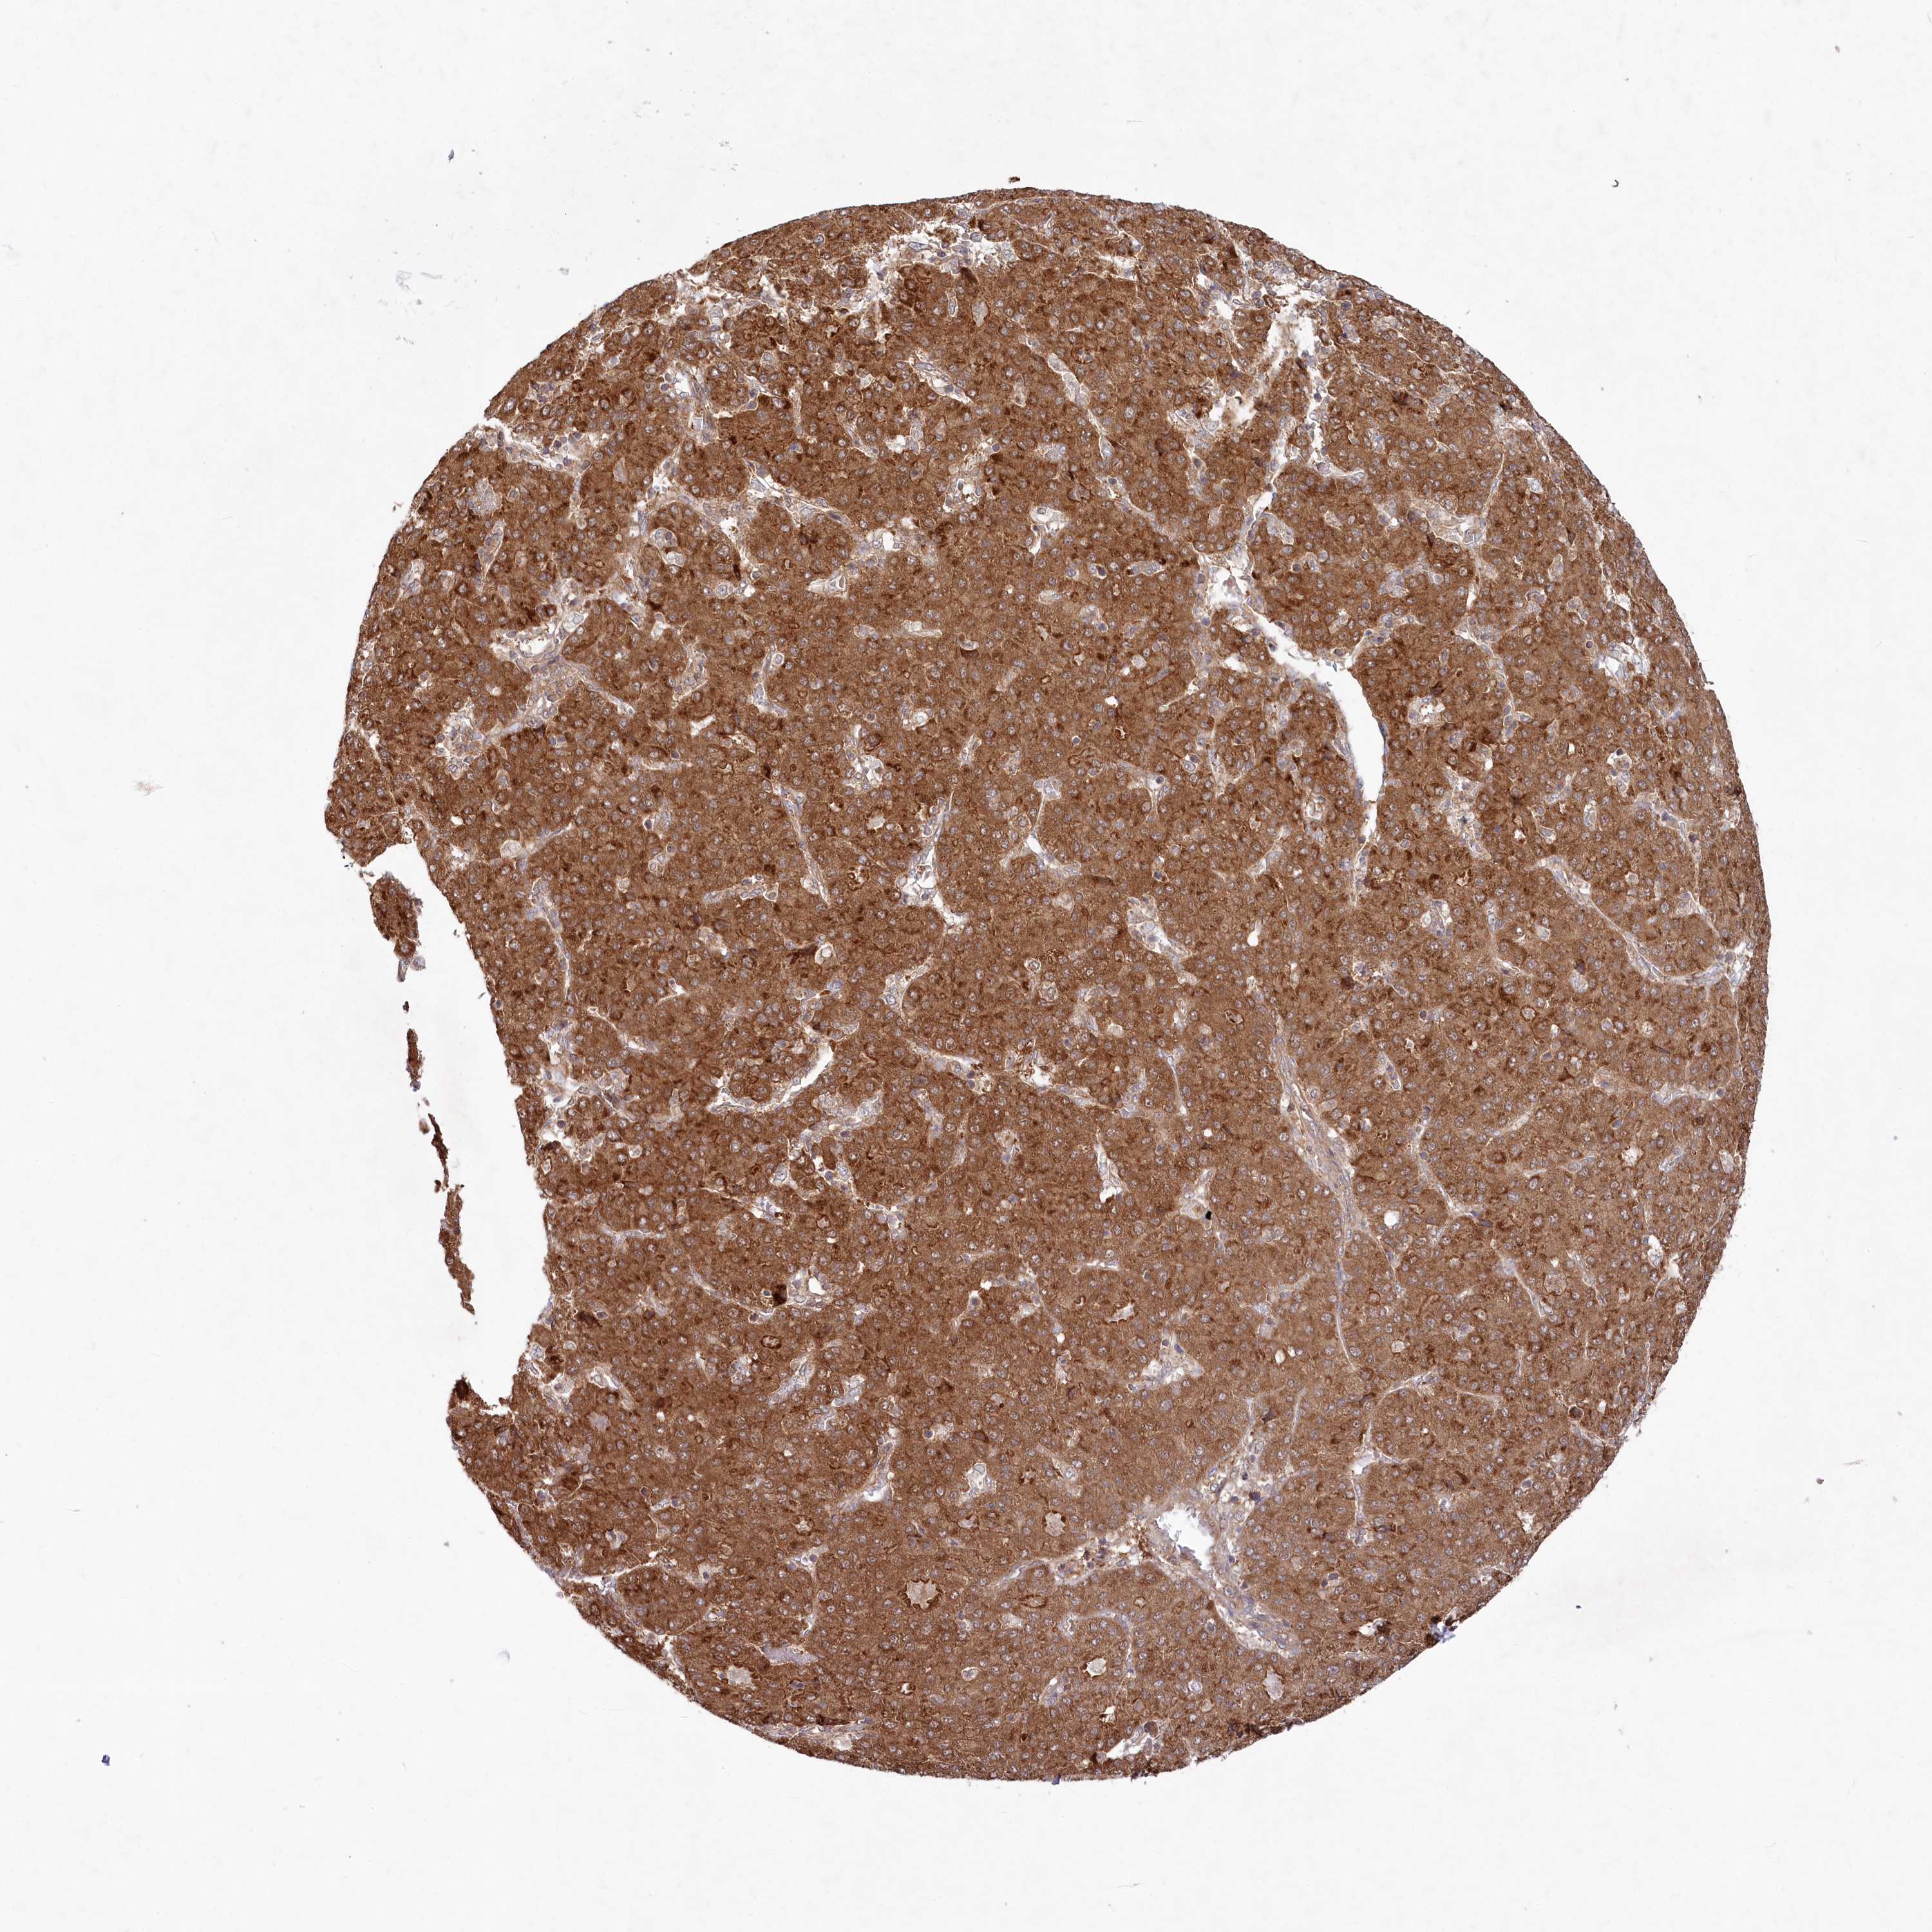

LIVER CANCER - Protein expressioni

A mouse-over function shows sample information and annotation data. Click on an image to view it in a full screen mode. Samples can be filtered based on level of antibody staining by selecting one or several of the following categories: high, medium, low and not detected. The assay and annotation is described here.

Antibody stainingi

Antibody staining in the annotated cell types in the current human tissue is reported as not detected, low, medium, or high, based on conventional immunohistochemistry profiling in selected tissues. This score is based on the combination of the staining intensity and fraction of stained cells.

Each image is clickable and will lead to virtual microscopy that enables deeper exploration of all samples and also displays staining intensity scores, fraction scores and subcellular localization as well as patient and tissue information for each sample.

Antibody HPA036487

Staining

High

Medium

Low

Not detected

Intensity

Strong

Moderate

Weak

Negative

Quantity

>75%

75%-25%

<25%

None

Location

Nuclear

Cytoplasmic/membranous

Cytoplasmic/membranous,nuclear

Cholangiocarcinoma

Carcinoma, Hepatocellular, NOS